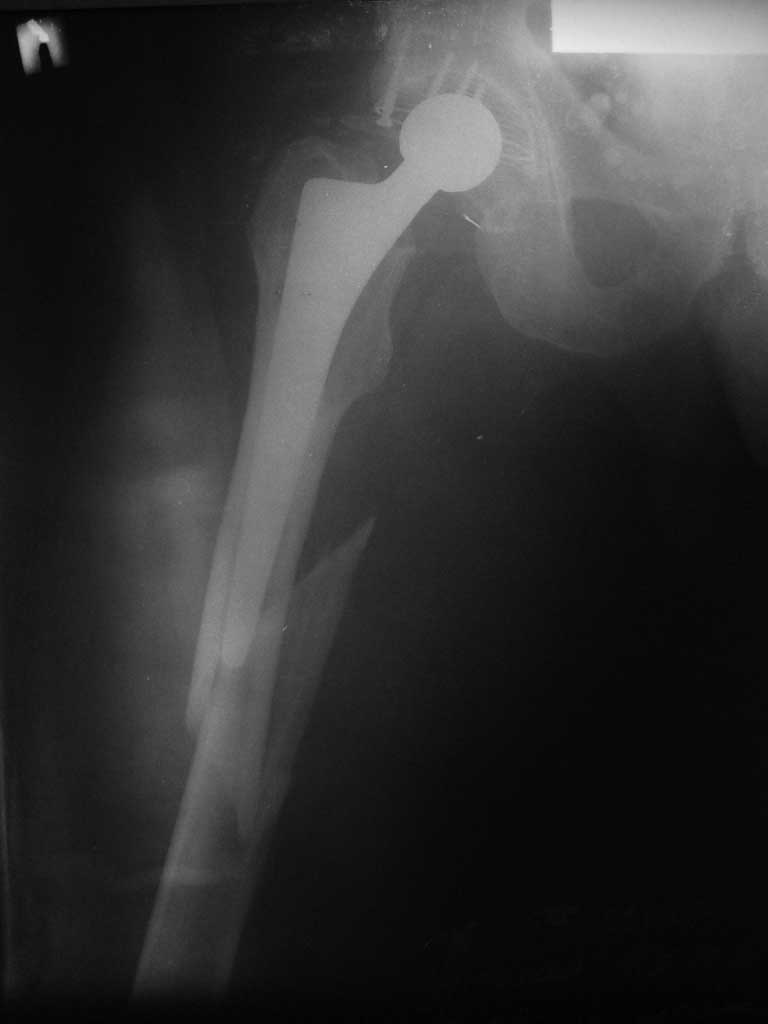

Произведено закрытое удлинение ножки эндопротеза с помощью ретроградного интрамедуллярного стержня. Продолжительность операции 3 часа. Два из них закрытое восстановление длины бедра диистрактором

таз-бедро.

А нельзя ли увидеть и профиль бедра на всем протяжении, т.е. и весь протез, и весь стержень? И фас бы с коленом.

новые снимки